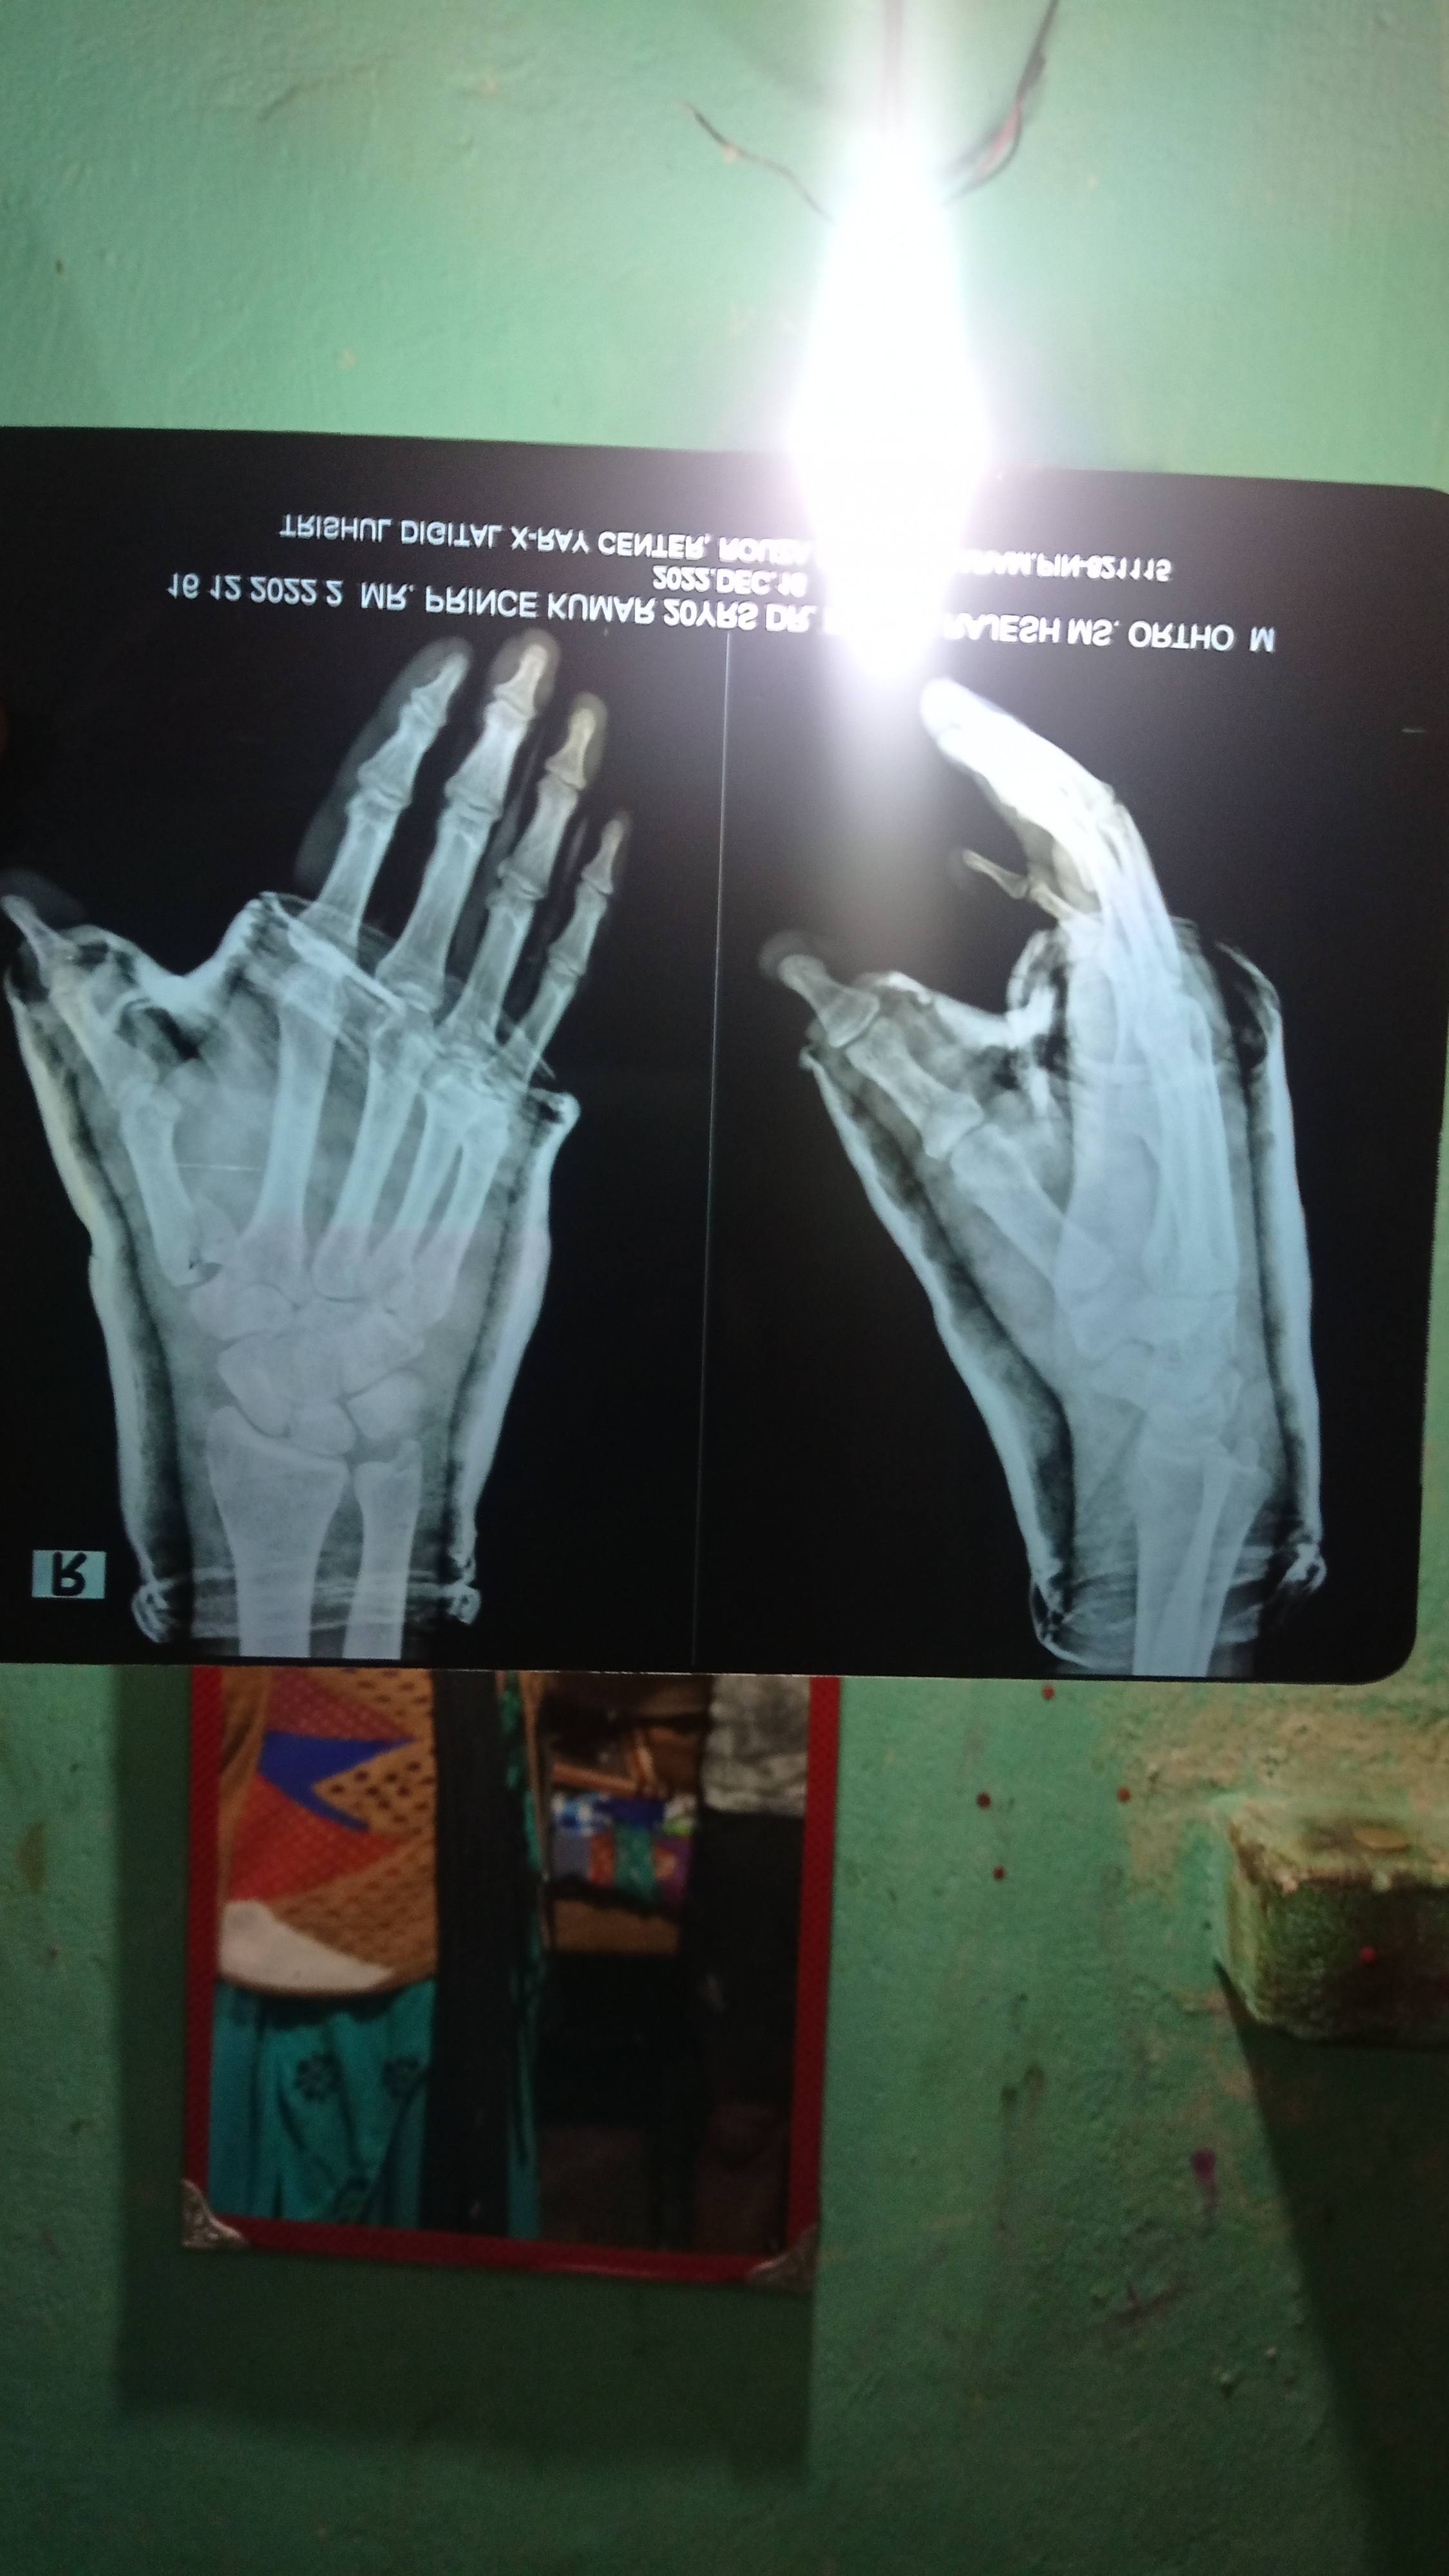

Sir humare yaha ka doctor plaster kr diya tha iske bad garam patti lga diya haddi bhi pakad liya h kuchh, ab kya kre sir